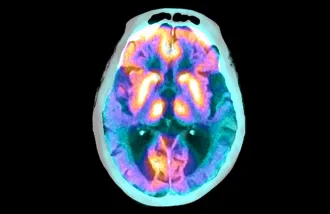

Dr. Poston’s research and clinical emphasis is to understand the motor and non-motor impairments, such as dementia, that develop in patients with alpha-synuclein pathology, such as Parkinson’s disease, dementia with Lewy Bodies, and Multiple System Atrophy. Her lab uses functional and structural imaging biomarkers, along with biological and genetic biomarkers, to understand the underlying pathophysiology associated these symptoms. Dr. Poston is Chief of the Movement Disorders Division and holds an appointment in the Memory Disorders division. She is a founding member of the Stanford Alzheimer’s Disease Research Center and co-Director for the Lewy Body Dementia Association Research Center of Excellence at Stanford University, and Director of the Stanford Parkinson’s Foundation Center of Excellence.